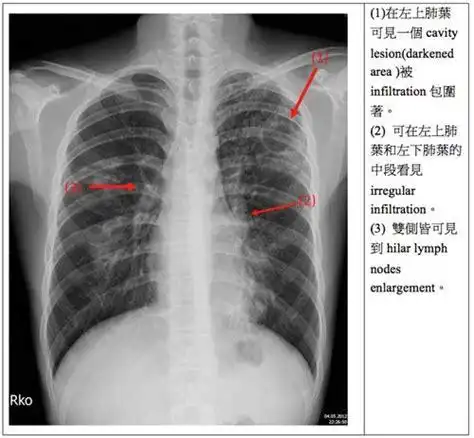

各型肺结核的典型影像表现